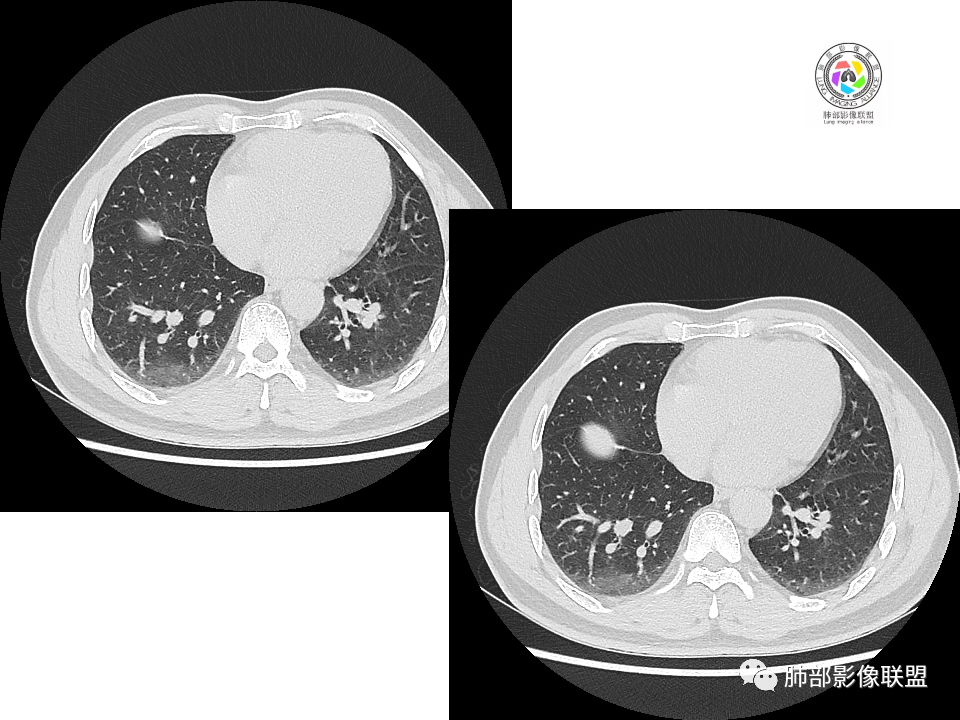

2.右肺下叶背段胸膜下块影,边界清楚光整,上下极见磨玻璃晕,未见明显分叶毛刺和棘状突起,未见胸膜凹陷或胸壁侵入。密度均匀,轻度不均匀强化。未见支气管进入。

3.右肺中叶外侧段胸膜下散在小片影,磨玻璃密度为主,边界不清,支气管相关。符合炎性特征!

4.右肺下叶基底段支气管血管束旁小结节影,边界清楚,强化不明显。注意,这结节在“遥远的”基底段。

3、卫星灶与“蘑菇兄弟”:诊断隐球菌时,建议找卫星灶,卫星灶可以在遥远的地方。可以是遥远地方的微小结节——“小蘑菇兄弟”。有些远处的卫星灶,通常是不规则饱满实性的,晕征不明显。隐球菌的卫星灶非常“隐”,但发现率高达60%多,诊断价值高。

4、卫星灶距离远的原因:隐球菌卫星灶常很远,推测:一次空气来源隐球菌感染进入双肺多处,部分定居繁殖;距离近的隐球菌“蘑菇兄弟”常常是二次感染。